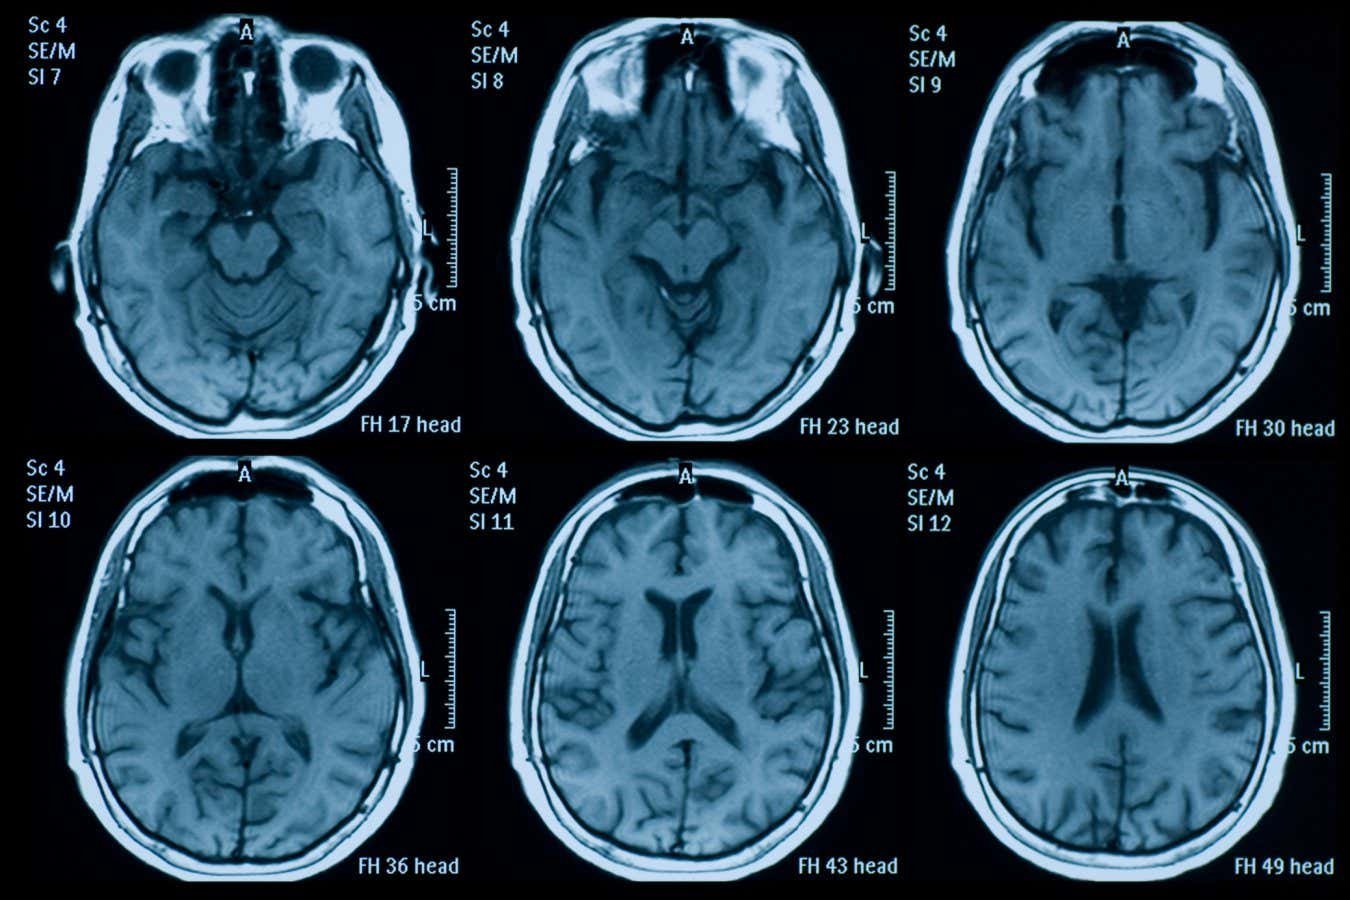

Structures within the brain change over time

Temet/Getty Images